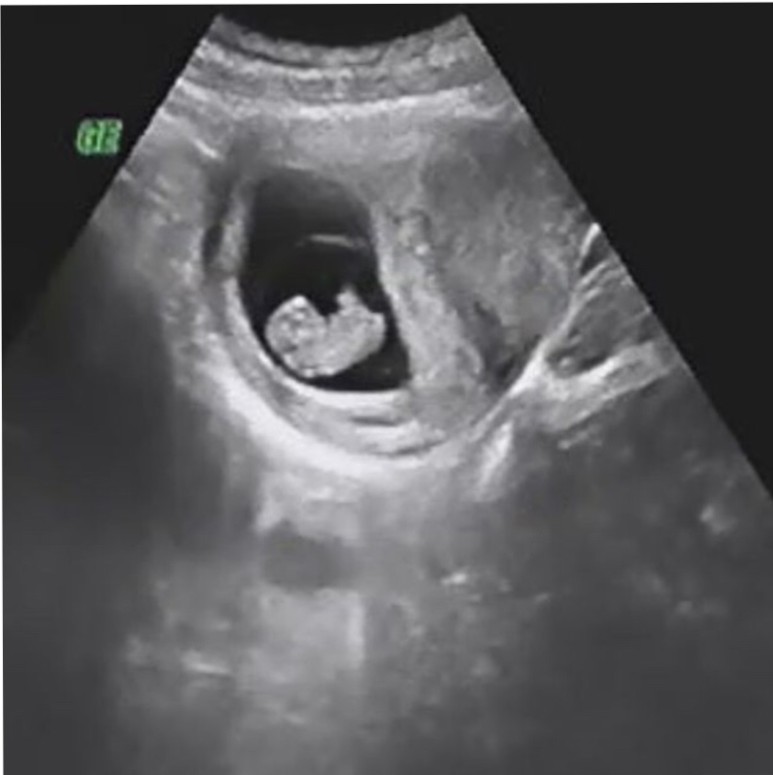

울트라니트라서 ♥강낭콩인줄…

2.29센치로, 지금까지 꽤 큰 튼튼함! 팔, 다리같은데 옆모습만 보여줘ㅜㅜ아무리 봐도 강낭콩으로밖에 보이지 않아.

젤리곰 사진 남겼는데 아쉽다.

심장음 188bpm으로 쿵쾅쿵쾅쾅쾅쾅쾅쾅쾅쾅쾅쾅쾅쾅쾅쾅쾅쾅쾅쾅쾅쾅쾅쾅쾅.